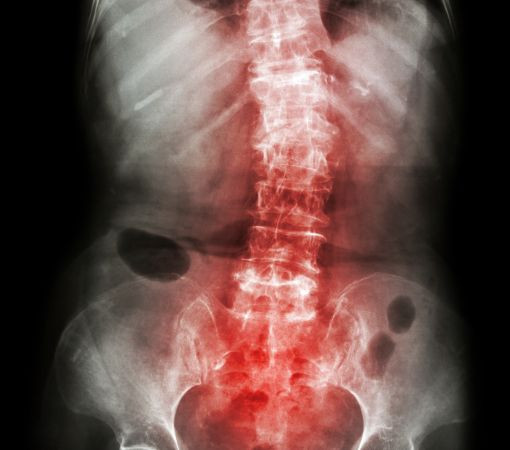

If you're dealing with the discomfort of spondylitis, finding the right specialist is essential to reclaiming your comfort and mobility. Synapse Spine offers advanced, comprehensive spondylitis treatment in Mumbai, with state-of-the-art facilities and personalized care plans tailored to each patient's unique needs. Spearheaded by Dr. Ganesh Nagarajan, a renowned expert in spine care, Synapse Spine is dedicated to offering effective, cutting-edge treatment options to help alleviate pain and improve your quality of life.

Spondylitis, an inflammatory condition that affects the spine and nearby joints, is typically managed through a combination of medication, physical therapy, and minimally invasive procedures. Dr. Ganesh Nagarajan and the team at Synapse Spine employ advanced imaging and diagnostic methods to accurately assess each case, ensuring that patients receive the right combination of therapies. Effective spondylitis treatment in Mumbai at Synapse Spine can include anti-inflammatory medication, guided exercise programs, lifestyle modifications, and, in severe cases, surgical intervention.